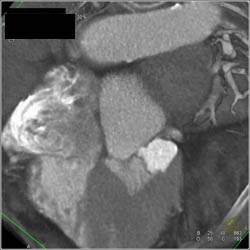

Aneurysm of Left Circumflex Coronary Artery